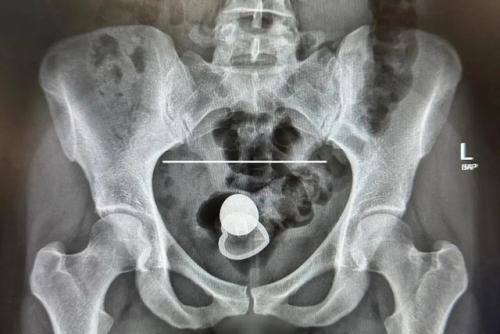

Алисия Дэвис провела два дня в больнице из-за застрявшего в прямой кишке предмета.

Хотя болей не было, она испытывала позывы и не могла удалить его самостоятельно. В итоге обратилась к врачам, которые успешно провели операцию